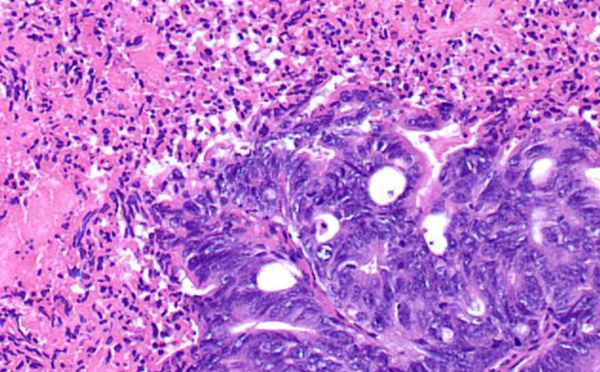

Utilizan modelos matemáticos para detectar diferencias metabólicas en tumores - 22/05/2015

Un equipo de investigación del Moffitt Cancer Center de EEUU ha desarrollado un modelo matemático que permite observar las características diferenciales de las células que forman un tumor. El conocimiento de estas diferencias permitirá una mayor comprensión del mecanismo con el que funcionan las células cancerosas, logrando así crear mejores tratamientos para los enfermos.